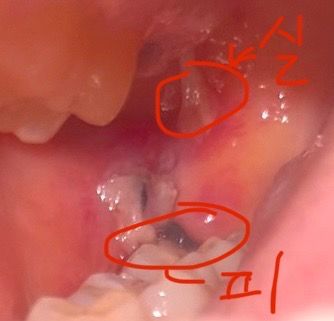

사랑니 발치 4일차 통증, 출혈, 혈병

위에 사랑니(정상) :

혈병이 떨어지려고 하고,

지금까지 아무 통증도 없다가 혈병쪽이 욱신거리고 아파요

저렇게 하얀 실 같은 조직도 생겨서 달랑거려요

아래 사랑니(수평 매복) :

실밥 밖으로 동그라미 친 부분에 피가 조금씩 새어나오고(이빨 틈에 약간 고일정도) 욱신거려요